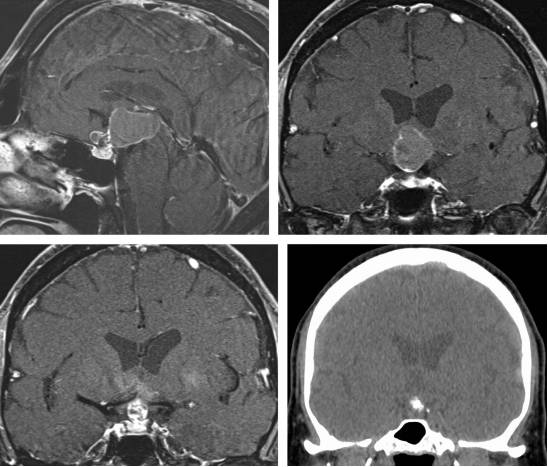

图2. 颅咽管瘤在MR图像上表现为不均匀的囊性和实质性信号(上图)。其囊性成分在T1相上表现为高信号,结节部分则表现为不均匀的显著强化(左下图)。CT上表现为点状钙化(右下图)。

图3. 图示为向四脑室延伸和压迫的蚓部毛细胞星形细胞胶质瘤。肿瘤呈囊性,伴有明显强化的结节。囊壁未见强化,无需手术切除。